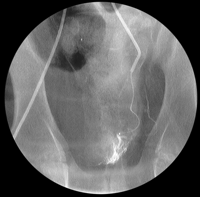

El procedimiento implica la localización de las arterias que brindan mayor irrigación a la próstata con el objeto de inyectar una resina capaz de producir la oclusión de la misma. El efecto de dicha embolización es la disminución sustancial del tejido prostático, aliviando los síntomas.

La desventaja es la gran vriación anatómica que existe, lo que dificutaría la identificación de la arteria prostática principal.